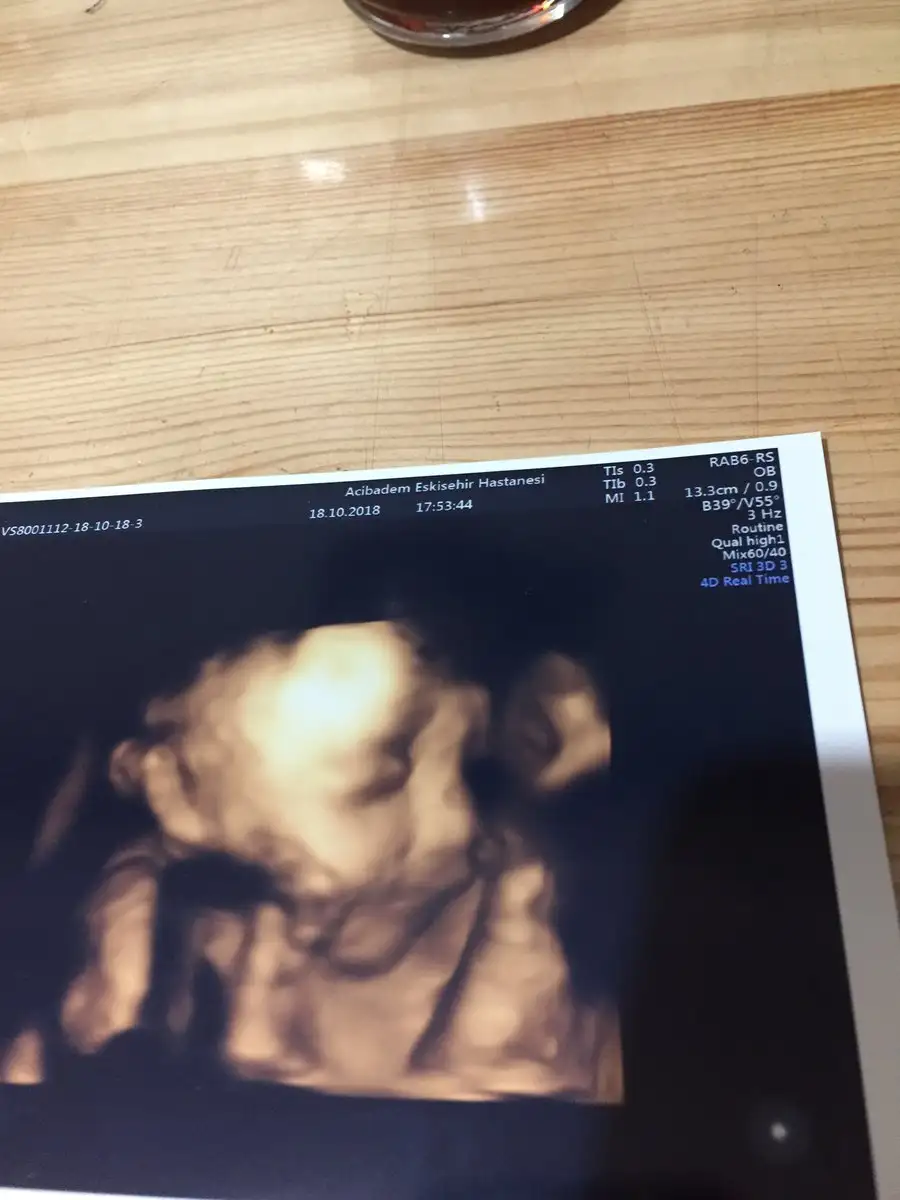

Oyyy minikkyaa bızım renklı pozlarımza bakın bugune dek bunları aldık 13haftalık biri dha 7cm orda

Bana da doktorum her gidişimde renkli görüntü verdi canım. Her defasında büyüdüğünü görmek çok güzel :)gecen bır arkadasıma da soyledım ankarada O. Ve gayet pahalı bır hastane. kadın renkli göstermemıs 17.haftada bıde dedım neden ses cıkarmıyorsun. ha şu da var benım hastaneme eşimın kuzenı gıdıyor o da daha alamamıstı onun dr.u baskası. nezaman verıyor dıye sordu bana benımkı verıyor dedım 13.haftadan buyana. dr.dan dr.a degısıyor demekkı canım![]()

evetttt yaaa resmen parmak kadarkenki halinden bebişliğe kadar olan sürecj göruyoruz nekadar şanslı bir donemdeyız kımbılır bızden sonra daha ne gelısmeler olacak şu teknolojide yerler onu pozlar hep aynı gb rahat glb ıcerde meleğinBana da doktorum her gidişimde renkli görüntü verdi canım. Her defasında büyüdüğünü görmek çok güzel :)